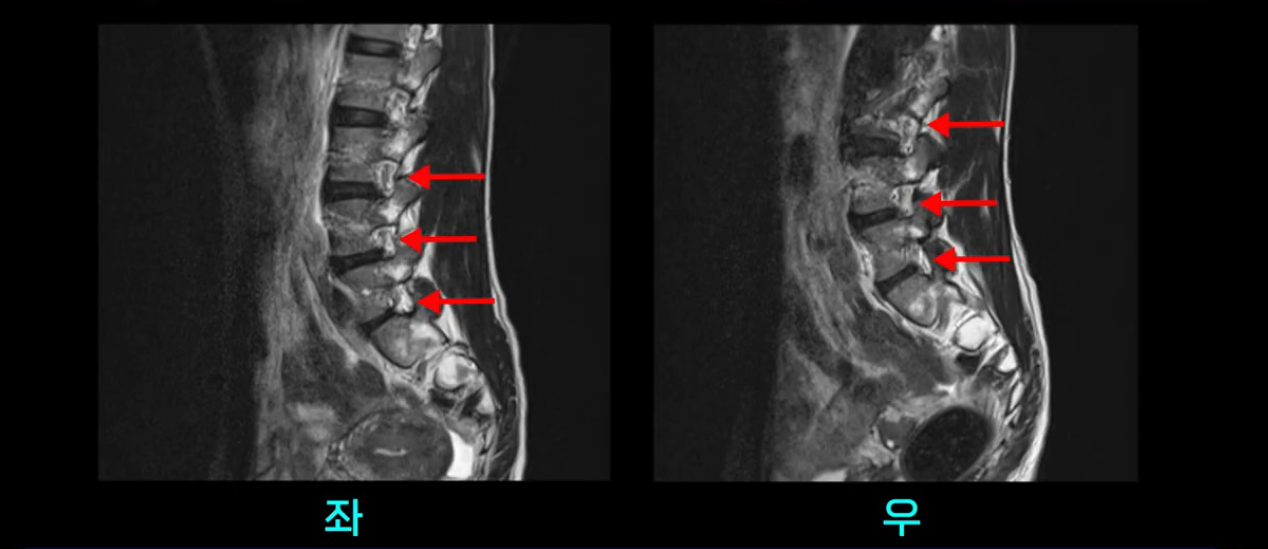

우선 이분의 MRI를 보고 먼저 설명을 드린 후 이런 환자분들의 통증의 원인은 무엇인지, 그리고 치료는 어떻게 해야 하는지 자세히 설명 드리겠습니다.

이분 MRI를 보시면 두 마디의 퇴행성디스크가 있습니다. 그리고 디스크가 조금씩 밀려 나와 있고요. 그런데 디스크 탈출 정도는 두 마디 다 심하지 않습니다. 4번 5번에는 디스크 탈출이 약간 있고,

척추관협착도 약간 진행이 되고 있고요.

5번 1번은 디스크 탈출이 가운데 쪽으로 살짝 있습니다.

또한 양쪽 신경 가지가 빠져나가는 추간공은 매우 넓은 상태입니다.

중요한 것은 이 정도 경미한 탈출과 협착으로는 양쪽 다리가 저리고 아플 수가 없습니다.

이분 MRI를 보시면 퇴행성디스크가 있고 약간의 협착이 있지만 이 정도의 퇴행성디스크와 협착으로는 신경이 눌려서 양쪽 다리가 저리고 아픈 증상이 나올 수가 없습니다. 그래서 MRI와 이 환자분의 다리 증상이 매치가 안 된다고 하는 의사들이 많은 겁니다.